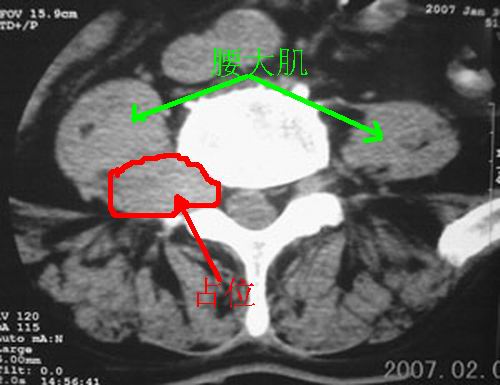

标题: CT8116:帮忙看这侧隐窝里是什么?男,75岁,腰周疼5-6年 [打印本页]

标题: CT8116:帮忙看这侧隐窝里是什么?男,75岁,腰周疼5-6年

男,75岁,腰周疼5-6年。别无症状。

考虑神经源性肿瘤可能大。依据:右侧神经孔扩大,相应部椎体压迫吸收。建议增强扫描,或mri平扫+增强。t1呈低等信号,t2呈高信号。增强后病灶(+++)强化。病灶内常见坏死。

右侧椎旁、侧隐窝软组织肿块,呈不规则双极征改变,椎体后外缘骨质弧形压迹,椎间孔扩大;考虑神经源性肿瘤,神经鞘瘤可能性大,需与神经纤维瘤相鉴别。

病变侧椎间孔扩大,椎体缘受压吸收;

考虑神经源性肿瘤,神经鞘瘤可能;

病变侧椎间孔扩大,椎体缘受压吸收,考虑神经源性肿瘤(神经鞘瘤可能)。